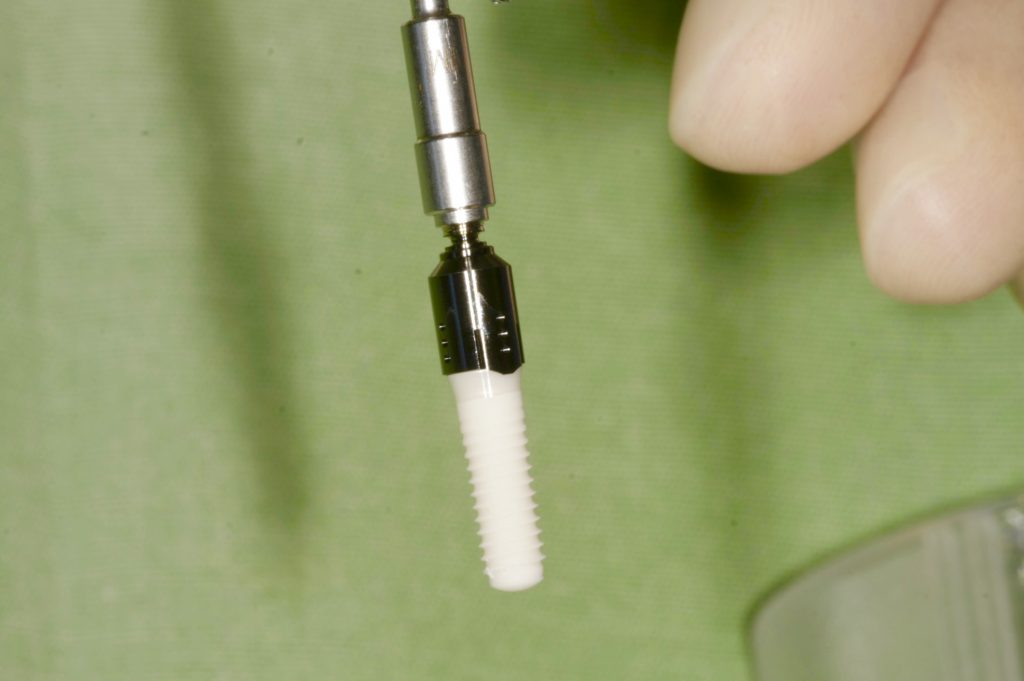

Autores: PRÓLOGO Asimismo, desde el punto de vista pedagógico, el profesional nobel en la materia tiene a su alcance la posibilidad de corregir cualquier posición implantaría en el ordenador, planear los provisionales y plasmarlos en la bio réplica antes de tocar al paciente a operar. Todos estos razonamientos nos llevan a presentar un caso de condiciones muy favorables para poner en práctica estos métodos como primer acercamiento a una Odontología Digital de alta calidad, con medios informáticos, que ya están presentes en la profesión de hoy en día, y será la protagonista única del futuro. Por otro lado, después de numerosos estudios que nos llevan a plantear el “gap” entre implante y pilar(abuttment), como principal responsable de la periimplantitis dado que la microbiota presente en el mismo es imposible de limpiar y en su presencia la cortical ósea reacciona reabsorbiéndose, nos ha llevado a utilizar implantes monobloc ya que los ejes implantarios y protéticos coincidían, y nos permitían su uso. Además, el circonio, ha mostrado a la luz de estudios muy recientes, una preservación y adhesión de los tejidos blandos superiores al titanio, tanto en su tratamiento de superficie de la rosca como a nivel gingival. DESARROLLO Paciente varón de 68 años, con antecedentes de radio/quimioterapia cinco años antes, con Rehabilitación Oral de los cuatro cuadrantes, con una Oclusión Mutuamente Compartida conservada, (REF.8) la que fracasa en el cuadrante 4, 19 años después. El mismo presentaba un puente de porcelana sobre circonio con pilares en 44 y 47, reemplazando el edentulismo de 45 y 46. Se produce la fractura del PM del 44, y ante una endodoncia antigua y corta, se decide implantar las zonas edéntulas, conservando temporariamente los pilares, hasta producida la oseointegración, para entonces también exodonciar el 44. DIAGNÓSTICO Tomamos impresiones del maxilar antagonista, Arco Facial Estático y realizamos montaje del mismo mediante la sistemática ARTEX. Producimos la relajación del músculo Pterigoideo Externo, para obtener la ORC (Oclusión en Relación Céntrica) mediante el método de Laminillas de Long, basado en el concepto de INERVACIÓN RECÍPROCA. Esto nos permitirá montar el maxilar inferior, tanto en su forma de: La primera para practicar la cirugía guiada y comprobar su eficacia, y el modelo de yeso para ser escaneado y confeccionar la GUÍA QUIRÚRGICA. La Biorréplica la obtenemos transformando los archivos DICOM que nos da el CBCT en archivos STL, y a partir de ellos, mediante una tecnología de PROTOTIPADO RÁPIDO, la obtención de un objeto físico en 3D a través de la aglutinación selectiva de una sucesión de capas de polvo. Procedemos a montar la biorrèplica y el modelo de yeso del caso. Podemos verificar la exactitud de las medidas del hueso residual en la bio réplica y compararlas con el scanner. Arrojando un resultado de 8,5 mm de cortical externa a cortical externa. Pudiendo también medir la distancia hasta el dentario. y comparar gracias a la ventana lateral de la biorréplica Dándonos 22mm de distancia. Con lo cual deducimos que implantes de 4,1mm por 12 mm serán perfectamente rodeados de hueso. Medimos también la distancia desde oclusal del antagonista, hasta el hueso desnudo. Lo mismo que, mediante la utilización de la guía radiológica, con un material radiolúcido colocado en gingival de la misma, podemos medir la altura de la encía. Con lo cual podemos calcular la altura del pilar. Es entonces cuando con el programa COC Diagnostix se realiza la programación final: Obteniendo no solo la ubicación, largo, ancho y ángulo de los implantes sino también los provisionales mediante CAD CAM. Ya entonces podemos hacer la práctica quirúrgica en la bio réplica, mediante la guía quirúrgica, instalando los implantes de prueba que no serán los de circonio, ya que la casa no cuenta con ellos, pero si otros de las mismas dimensiones. TRATAMIENTO Entramos ya en la cirugía propiamente dicha. Antisepsia de la zona a operar y zonas anexas. Comprobación del perfecto ajuste e inmovilidad de la G.Q. en boca durante la cirugía. Marcado de la encía y perforación de la cortical. Visión a través de la Guía de la mínima intervención anterior. Comprobación sin Guía. Incisión mínima mesio distal, para apartar y conservar encía queratinizada. Secuencia de drills, perforando a profundidad requerida Observación del Mínimo Trauma Implantes Strauman de Zirconio Monoblock en blíster y montádo en contrángulo reductor. Instalación controlando torque con contrángulo reductor. Comprobación clínica. Comprobación Radiográfica y con Guía. Toma de impresiones, y armado de modelos con técnicas de pasividad protética. Montaje. Resultado de las provisionales ejecutadas por CAD CAM Al no estar conformes con el resultado decidimos desechar dichas provisorias y optar por repetirlas. Nuevas provisorias realizadas mediante encerado convencional. Estado de los tejidos blandos. Provisorias en boca. Oclusión de Estímulo Inmediato. Ref.10: Carga inmediata .Alberto y Diego Bechelli. Comprobación mediante CBCT post operatorio Componentes del equipo (En la próxima presentación, mostraremos las coronas definitivas de porcelana sobre circonio, y la desoclusión provocada por una OCLUSIÓN MUTUAMENTE COMPARTIDA, sobre estos implantes y otros seis mas) REFERENCIAS

FIG: 35-36-37-38-39-40-41

Fig. 35

Fig. 36

Fig. 37

Fig. 38

Fig. 39

Fig. 40

Fig. 41

FIG:55

FIG:56

FIG:57

FIG:58